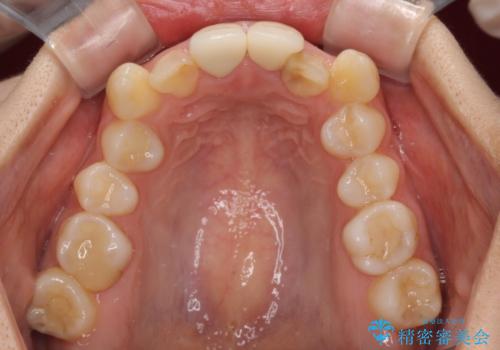

- 学生の頃に神経を取り除いた前歯の変色と、色合いの悪いかぶせ物が気になるとのことで来院された患者様です。

レントゲン写真より、歯根の炎症が認められず、土台もしっかりと植立されていたため、仮歯に置き換えた後にオールセラミッククラウンにて補綴することとしました。

矯正治療を行うかどうかは相当悩まれており、セラミッククラウンが装着されるまで、本当に良かったのかと心配されていましたが、とてもきれいな口元に仕上がり、大変満足していただけました。